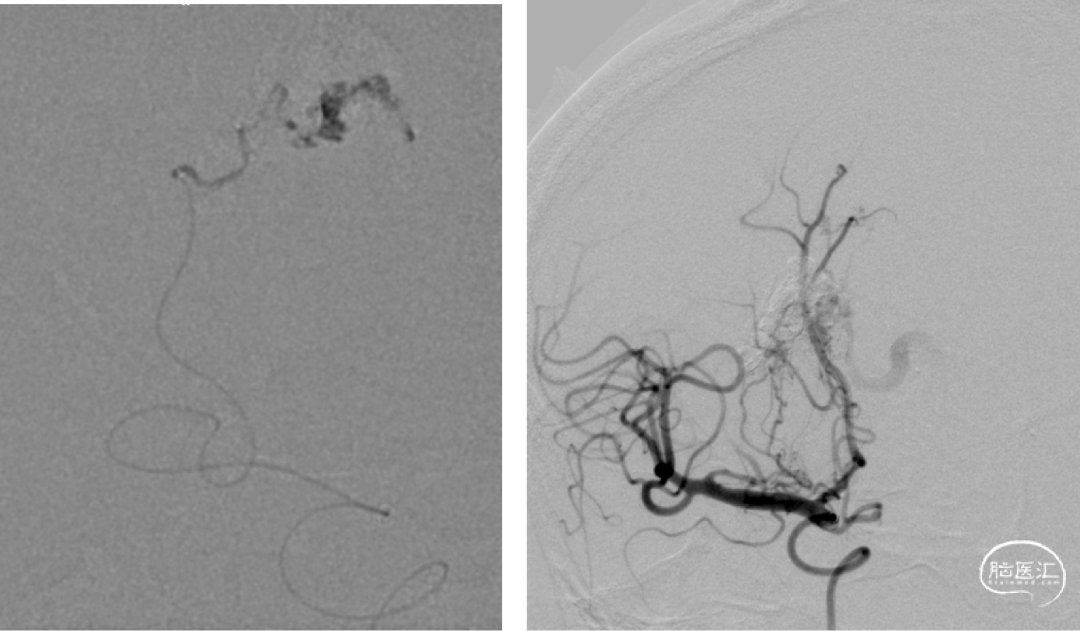

术前DSA:右侧基底节动静脉畸形,豆纹动脉供血,经大脑静脉、直窦、横窦、乙状窦引流

术前DSA